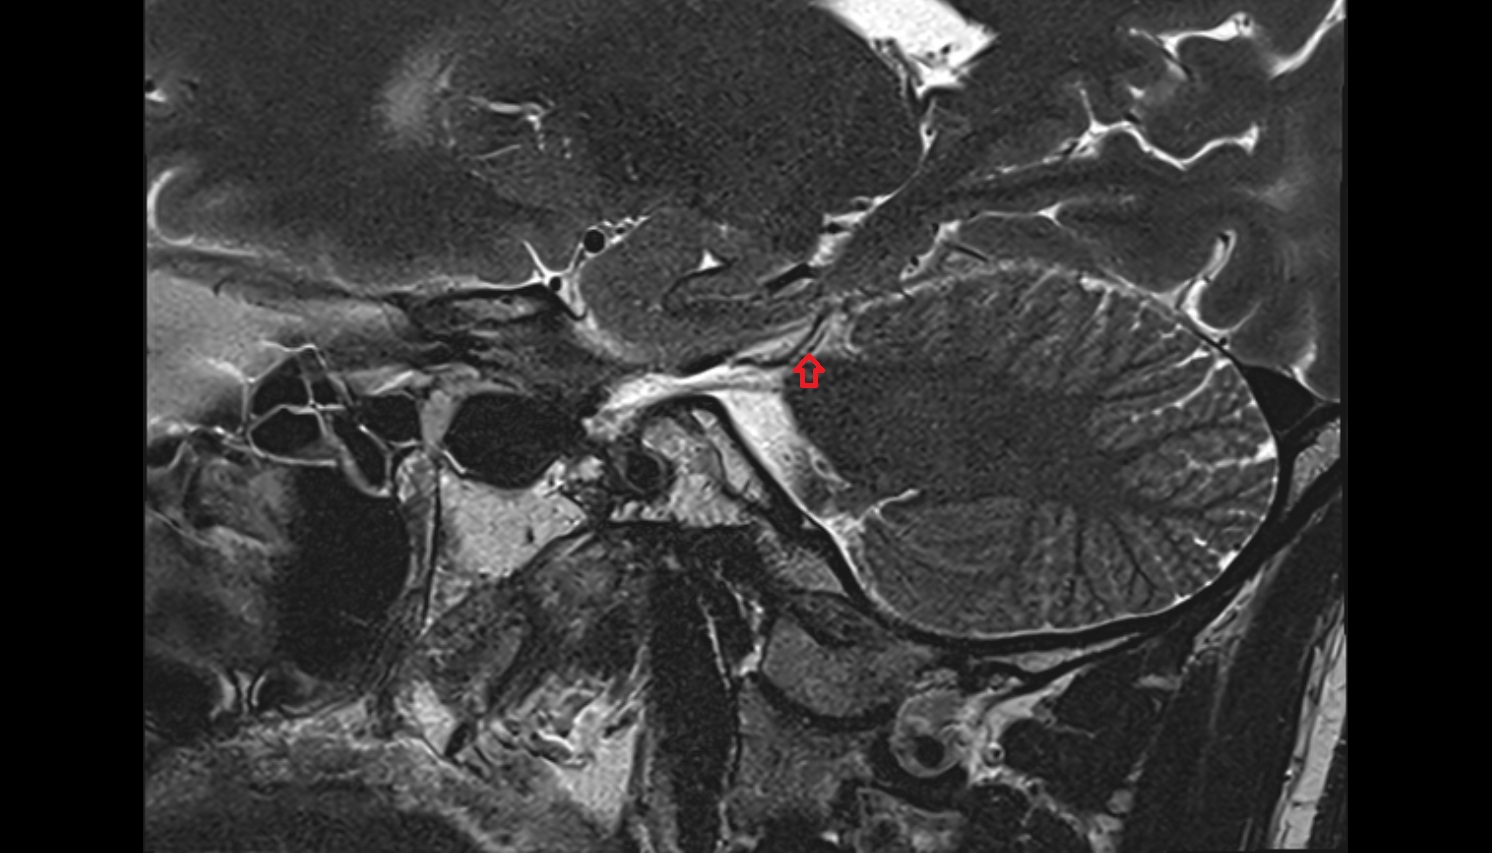

- Temporomandibular joint

- Articular disc of temporomandibular joint

- Articular eminence

- Mandibular condyle

- Mandibular fossa